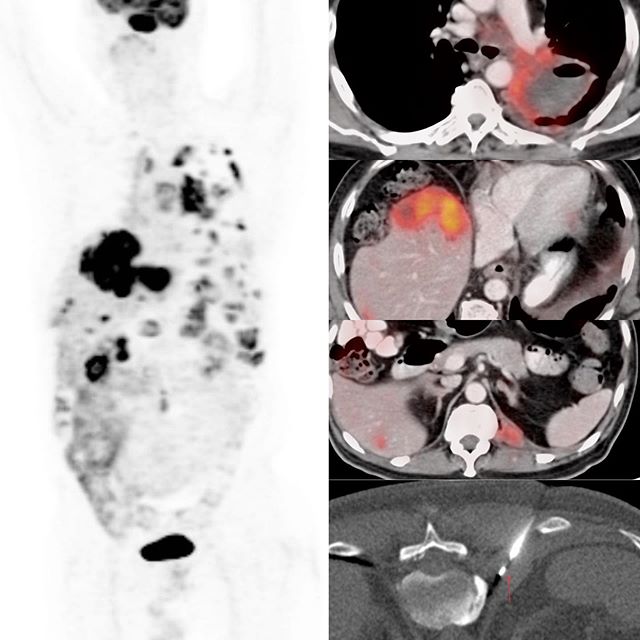

This is a 62-years old man with a large necrotic left hilar mass with brain, liver, and pleural metastases.

The issue here is not to just diagnose the adenocarcinoma, which this turned out to be, but to also get adequate material for EGFR, ALK, PDL1, ROS1, etc. I could have biopsied the left hilar mass, but I was not confident that given the amount of necrosis, I would get adequate material. The same was the argument for the large liver lesion.

The left pleural nodule was small, but non-necrotic and using an 18G coaxial biopsy gun, I could ensure at least 10-12 good cores that would suffice for all the investigations that this patient would need.